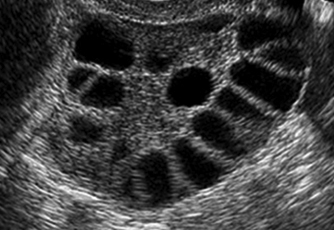

Ovarian hyperstimulation syndrome can develop when too many follicles (sacs containing the eggs) grow as a result of the hormone injections used in fertility treatments. The main symptoms are:

- If you have a high antral follicle count (AFC), or a large pool of resting follicles.

- Antral follicle count (AFC): The number of resting follicles that are waiting to enter the final growing phase towards ovulation. This measurement is used as one of the ways of predicting how an ovary may respond to IVF hormone stimulation.

- Polycystic Ovary Syndrome (PCOS): A hormonal disturbance which causes subfertility mainly by causing the periods, and therefore ovulation, to become irregular. Polycystic ovaries typically have many follicles (egg sacs) waiting for the hormonal message to start growing. Sometimes too many will take off as the same time and increase the risk of OHSS developing.